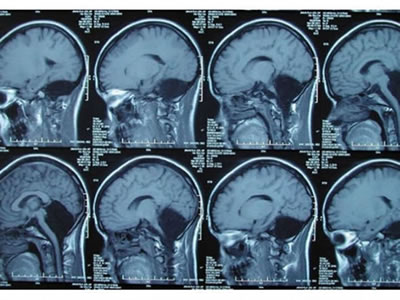

Cérebro: problemas no cerebelo podem levar a comprometimento mental, distúrbios de movimento e epilepsia (Foto: Feng Yu et al )

Uma tomografia computadorizada identificou a origem do problema: ela não tem cerebelo, que representa cerca de 10 por cento do volume total do cérebro e contém 50 por cento dos neurônios. Essa parte do cérebro estabelece o equilíbrio corporal, recebe estímulo de músculos e tendões, além de controlar atividades motoras.

Problemas no cerebelo podem levar a grave comprometimento mental, distúrbios de movimento e epilepsia. No entanto, nessa mulher, a falta de cerebelo resultou em apenas em leve deficiência motora e de fala.